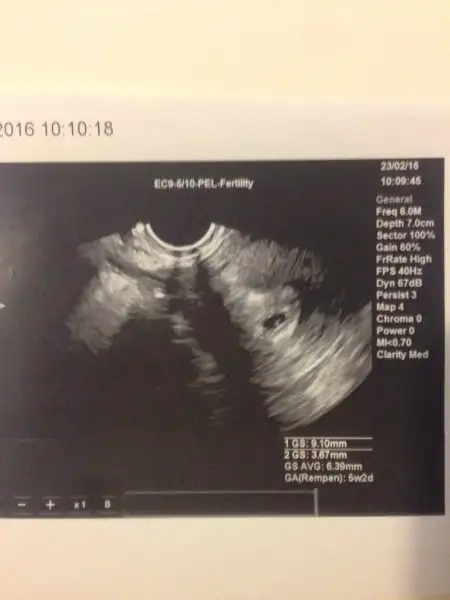

Rabbim sağ salim kucağımıza almaya nasip etsin benim de böyleydi dünBenim ilk ve şimdiye kadar ki tek muaynemde kese göründü içinde de bebek var mıydı bilmiyorum ki ben heycandan sormadım ama ultrosom bu anlaşılıyor mu bilmiyorum ama

. Eki Görüntüle 1783416

zor seyler yasamıssın Allah tekrarını yasatmasın canım.. Tabıkı bır olumsuzluk oldugunda Allah korusun ınsan bır kısıye ınanamaz. Senın keseyı gordugunde daha buyukmus canım benım tahmınen daha kucuktur haftaya gıdersem o kadar olur ıste :) adetın duzensız olmasıda kotu bu anlamdao zamanda tek doktora inanmayıp başka doktora gitcen canım bi doktora sonuna kadar güvenmekte iyi değil ben 1 hafta sancı çektim gece kalkıp ağlıyordum ama doktor bana Kum döküyorsun dedi Kum sancısı diye geccek bebeğim diye diye konustum bebegimle avuttum kendimi 1 hafta sonunda su kesem geldi her şey için çok geçti benim çektiğim Kum sancısı falan değil doğum sancisiymis. şimdi doktoruma güveniyorum ama sonuna kadar değil bi olumsuzluk olursa onla yetinmeyip başka doktora da gitcem. ben 5+6 da keseyi gördüm bugün 7 oldum tam 7+5 te gitcem ama keseyi gördüğünde doktora satla uyumlu mu diye sormadım benim hesaplarimca böyle haftası :) karından bakıldı canım

Ultrasonda görünen tarih ile SAT'a göre hesaplanan tarih farklılık gösterebiliyor. Ben de 7+1 diye gitmiştim 6+1 çıktım ultrasonda canım. Farklılık olabiliyormuş, geç döllenme vs. filan demişti benim doktor. Sen oldukça dikkatli ol arkadaşım, doktorun dediği gibi asla kendini yorma, merdiven bile çıkma.. Allah'ım sağlık sıhhatle bebişlerimize kavuşmayı nasip etsin inşallah.